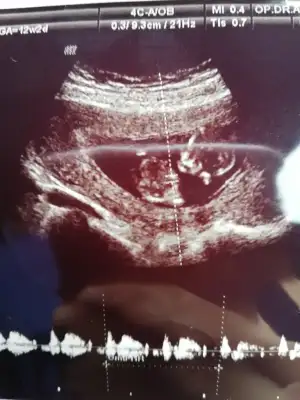

Doktor %80 erkek dediTamam kız bu bebiş.kesin kız![]()

Bence kız.bir sonraki kontrolde daha da kesinleşecektir.ben ısrarla kız diyorumDoktor %80 erkek dedi

Siz erkek istiyordunuz galiba.nub çizgisine ve kafa yapısına göre yorum yapıyorum.cinsiyet oluşmadan önce nub çizgisi oluşur.bu çizgi paralelse kız,dik ise erkek demektir.sizin bebeğinizin nub çizgisi bariz paralel.kafa yapısı da oval.erkeklerin kafa yapısı daha yuvarlak olur. Doktor kesin erkek dedi mi size? Buda cinsel organı diye gösterdi mi? Kaç haftalıksınız şuan?Doktor organını bile gösterdi bu çıkıntı olabilir diye yine de cevabınız için teşekkür ederim merakımdan soruyorum yanlış anlamayın neye göre Tahminde bulunuyorsunuz mesela son resim tam olarak neyi gösteriyor hiçbirşey anlamadım

Evet gönlümden geçen erkek Bi tane kızım var çok ta sevinmiştim siz şimdi kesin kız deyince moralim bozuldu biraz. Şu an sat a göre 11 hafta 6 gün usg ye göre 12 hafta 6 gün. Doktor erkeğe çok benziyor çıkıntısı burada diyerek gösterdi kesin erkek demedi yüzde 80 erkek dedi ama bazen kızlarda da bu çıkıntı oluyor dedi. Hatta bu Nub teorisinden de bahsettim belli olmaz bazen dik bazen paralel bile olabilir dediSiz erkek istiyordunuz galiba.nub çizgisine ve kafa yapısına göre yorum yapıyorum.cinsiyet oluşmadan önce nub çizgisi oluşur.bu çizgi paralelse kız,dik ise erkek demektir.sizin bebeğinizin nub çizgisi bariz paralel.kafa yapısı da oval.erkeklerin kafa yapısı daha yuvarlak olur. Doktor kesin erkek dedi mi size? Buda cinsel organı diye gösterdi mi? Kaç haftalıksınız şuan?

Erkek gibi.duruş pozisyonu dik olunca kız mı erkek mi karar veremedim açıkçası.ama oyumu erkekten yana kullanıyorum. Kız da olabilir ama.ay emin olamadım bu usg deyok yok kız bu

Kızlarda da bu çıkıntı oluyor dediyse nub çizgisinden bahsediyor.11 12 haftada cinsel organ tam anlamıyla oluşmuyor nub çizgisi oluyor.13 14 haftalarda organ oluşmuş oluyor.yani direkt olarak pipi göstermemiş.bilmiyorum doktor erkek dediyse erkek olabilir.ben bariz kız görüyorum bu usg de.elbette doktorlar daha iyi bilir tabi.rabbim gönlünüzdekileri nasip etsin inşallah.siz sorduğunuz için cevapladım.ama bana göre bu bebiş kızEvet gönlümden geçen erkek Bi tane kızım var çok ta sevinmiştim siz şimdi kesin kız deyince moralim bozuldu biraz. Şu an sat a göre 11 hafta 6 gün usg ye göre 12 hafta 6 gün. Doktor erkeğe çok benziyor çıkıntısı burada diyerek gösterdi kesin erkek demedi yüzde 80 erkek dedi ama bazen kızlarda da bu çıkıntı oluyor dedi. Hatta bu Nub teorisinden de bahsettim belli olmaz bazen dik bazen paralel bile olabilir dedi